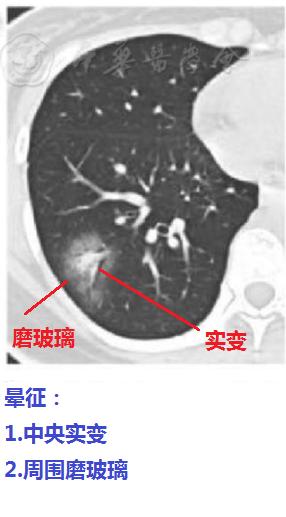

图17

很多疾病都会出现晕征和反晕征,但是有一点,普通的肺炎很少出现晕征和反晕征,这对鉴别新冠肺炎还是比较有价值的。

下面是新冠肺炎患者肺部晕征和反晕征的表现,如果不告诉你们能区分开吗?

第1张是新冠肺炎的晕征,普通的肺炎很少表现为这样。

图18

第2张是新冠肺炎的反晕征,普通的肺炎也很少有这样的表现。

图19